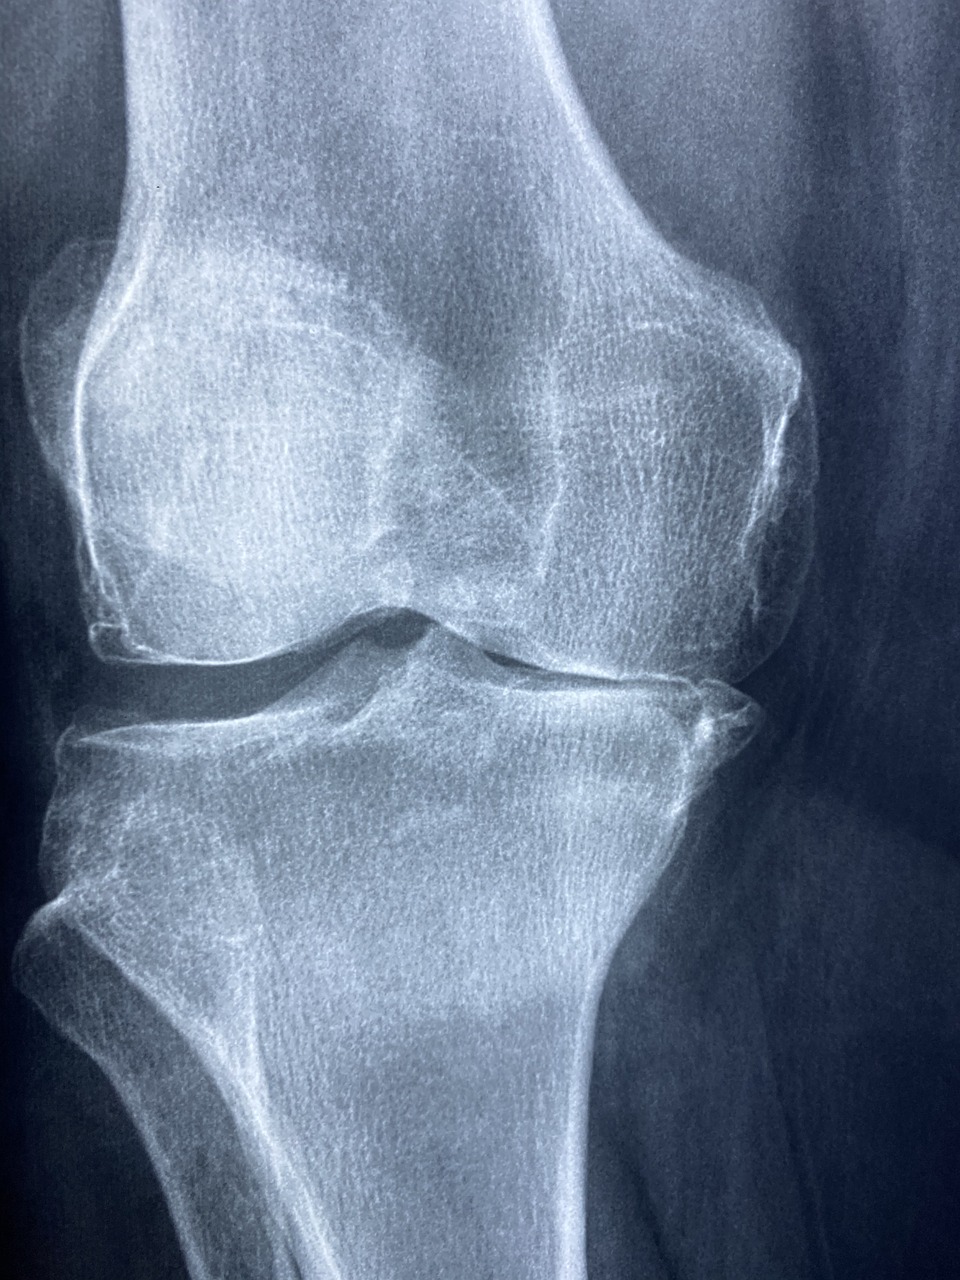

퇴행성 관절염(골관절염)은 관절의 연골이 점진적으로 닳아 없어지는 질환으로, 주로 노화로 인해 발생하지만 다양한 원인에 의해 발병할 수 있습니다. 본 글에서는 퇴행성 관절염의 주요 증상과 발생 원인, 최신 치료법, 그리고 효과적인 예방법에 대해 자세히 알아보겠습니다.

퇴행성 관절염은 관절의 퇴행성 변화로 인해 다양한 증상이 나타나며, 특히 무릎, 손, 엉덩이, 척추 관절에 자주 발생합니다. 주요 증상은 다음과 같습니다.

염증이 생기면서 관절이 붓거나, 심한 경우에는 관절의 모양이 변형되기도 합니다. 특히 무릎 관절이 O자형이나 X자형으로 변형되는 경우가 많습니다.